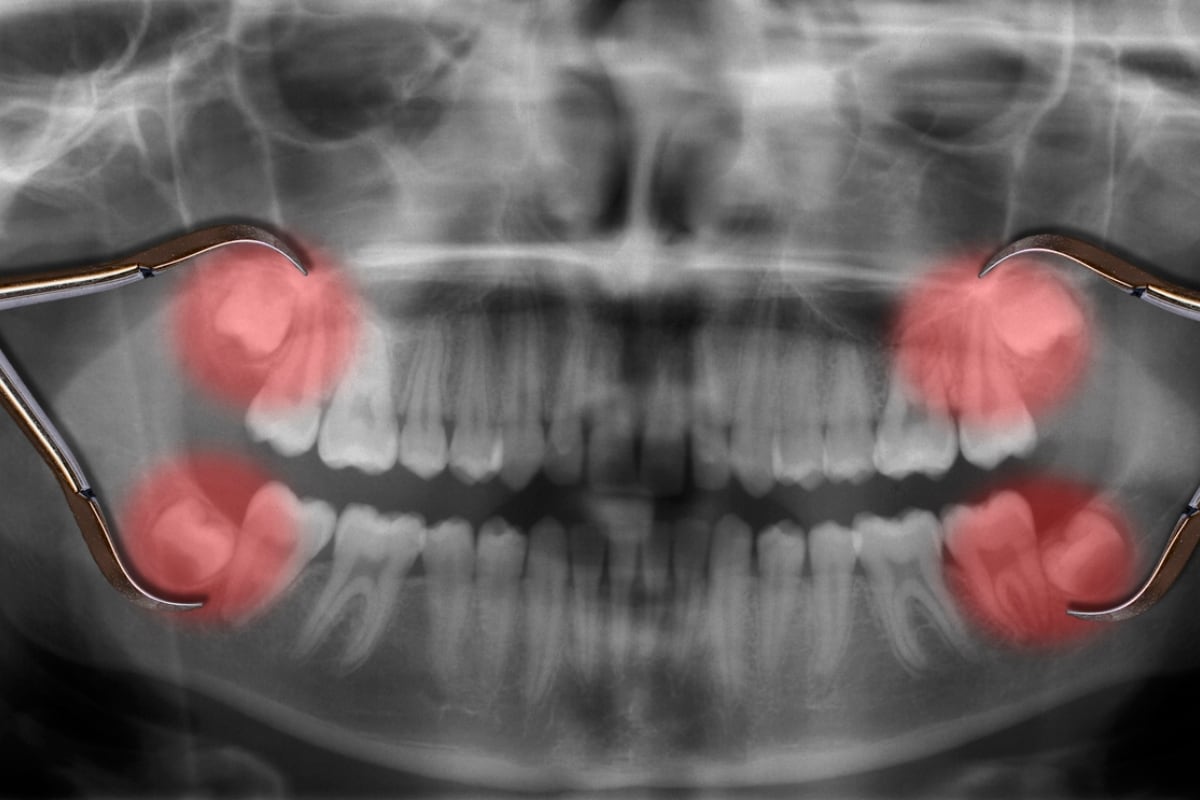

Las muelas del juicio, que son los terceros dientes molares o cordales de la boca, llevan ese nombre desde hace siglos.

El nombre significa que estos dientes de la parte posterior de la boca (anchos y de corona aplastada que trituran los alimentos) suelen brotar durante una etapa de la vida en que las personas son más maduras y sabias que en su juventud.

Al aparecer por lo general entre los 17 y 24 años, la creencia popular, que llevó al nombre, considera que se ha dejado atrás la niñez y la adolescencia —etapas de despreocupación— y se ingresó a una nueva fase de la vida en que se tiene pleno raciocinio y juicio propio sobre cosas y situaciones.